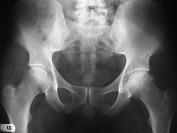

问题 女,60岁,髋部疼痛、活动受限、跛行,请结合图片像,选出最可能的诊断 ( )

选项 A、退变性囊肿 B、暂时性骨质疏松 C、髋关节结核 D、股骨头缺血坏死 E、骨岛

答案 D